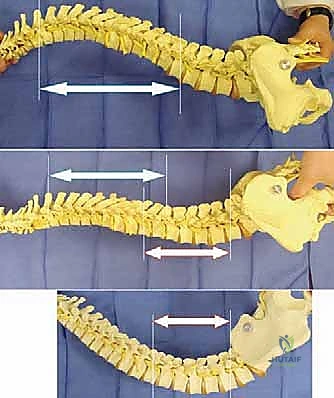

Biomechanically, the unit rod construct is a masterpiece of load-sharing and stress distribution. By utilizing a single, continuous, pre-contoured rigid rod (typically 1/4 inch or 3/16 inch stainless steel) and securing it at every available segmental level with sublaminar wires, the construct dissipates corrective forces across the entire length of the spine. This minimizes the stress concentrated at any single bone-implant interface, drastically reducing the risk of implant pullout in osteopenic bone. The primary corrective maneuver is a powerful cantilever force. The distal limbs of the unit rod are first docked into the ilium. The proximal U-shaped portion, which initially stands proud of the kyphoscoliotic thoracic spine, is then gradually leveraged down to the midline. This maneuver translates the spine to the rod, simultaneously correcting the coronal deformity, restoring sagittal contours, and forcefully leveling the pelvis.

The correct width of the U-rod is selected to sit comfortably across the laminae. The rod is then introduced to the sterile field. The distal limbs are simultaneously impacted into the bilateral iliac holes. At this stage, the proximal U-portion of the rod will be standing high above the thoracic spine due to the uncorrected deformity.

5. The Cantilever Reduction Maneuver

With the pelvis securely docked, the cantilever reduction begins. The surgeon forcefully pushes the proximal U-portion of the rod down toward the thoracic spine. This maneuver requires significant physical force and utilizes the rod as a massive lever arm.

As the rod is brought down to the spine, it translates the apical vertebrae toward the midline, correcting the scoliosis, while simultaneously forcing the elevated hemi-pelvis down, correcting the pelvic obliquity.